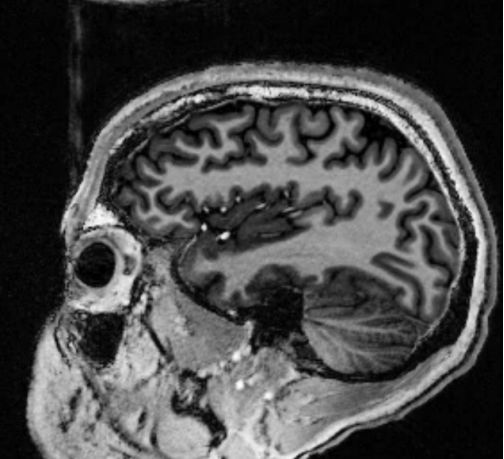

这导致了两个结论,首先,人工智能系统的功能类似于人类大脑中的神经活动,其中信号\传感器数据的强度与其自身连接结构行为一样重要。